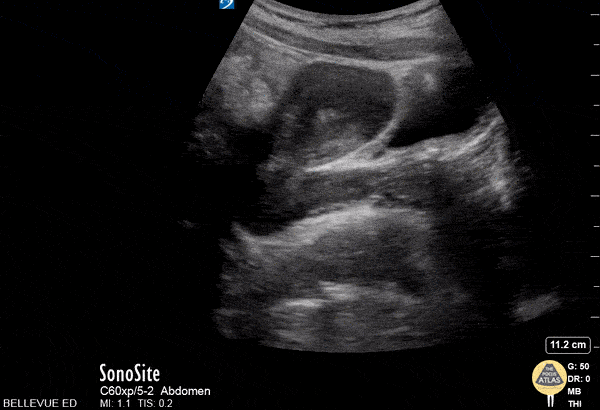

OB/Gyn - Transabdominal Left Adnexa

In this transabdominal view of the uterus in transverse, we see the left fallopian tube branching off the uterus leading to the left ovary in which multiple small hypoechoic follicles are visible, giving the ovary its typical “chocolate chip cookie” appearance. At the end of the clip, one of the left iliac vessels is seen in long axis just deep and lateral to the ovary. The bright hyperechoic lines with dark shadowing in the surrounding fields are bowel gas. Hannah Kopinksi and Dr. Lindsay Davis - NYU Emergency Medicine